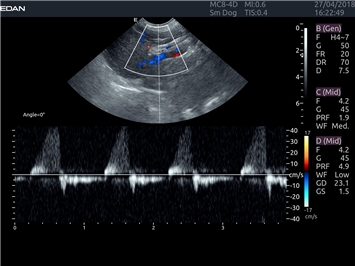

EDAN Acclarix LX4 VET

EDAN Acclarix LX4 VET представляет собой профессиональную ультразвуковую систему, специально разработанную для ветеринарных исследований. Сочетание стабильности, высокой производительности и эффективности делает эту систему идеальным выбором для современной ветеринарной практики.

Цветовой допплер:

Да

Импульсно-волновой допплер: